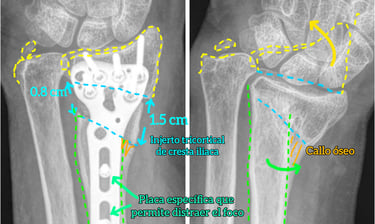

Artroscopia de muñeca

Cirugía mínimamente invasiva para la patología más compleja de la muñeca